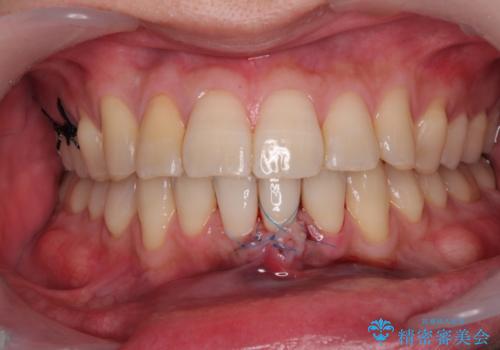

歯肉退縮に対して、上顎からの結合組織移植術(CTG)により、歯根の被覆を行うとともに、歯肉の厚みを増すことで将来の退縮リスクを抑制することとしました。

被覆量が不十分の場合には、追加で手術を行うことで患者様の了解を得ました。